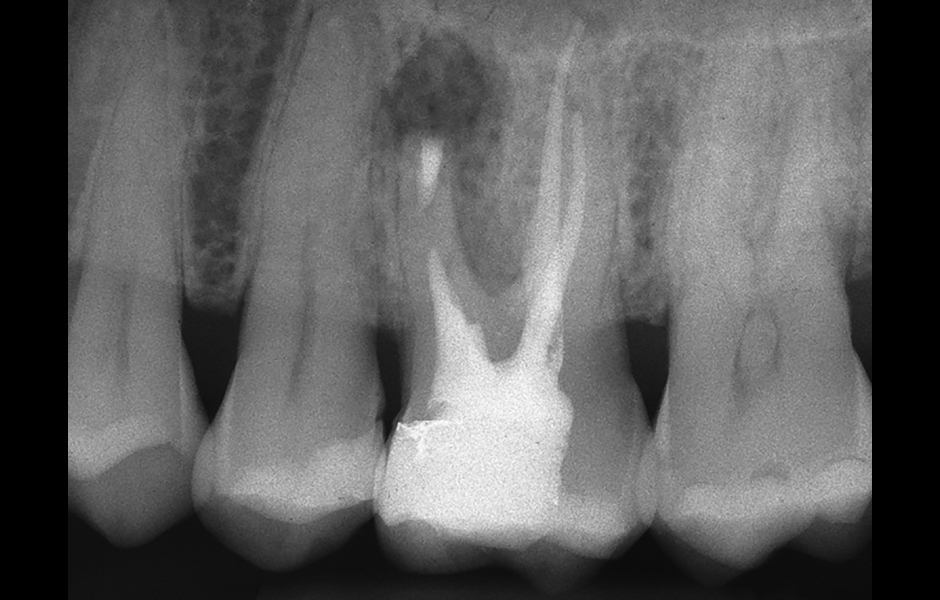

Obr. 2.8: Pooperační rentgenový snímek zobrazující obě retrográdní výplně.

Obr. 4.1: Předoperační snímek horního levého prvního moláru. Oba kanálky mesiobukálního kořene byly kompletně kalcifikované a nebylo možné je ortográdně zprůchodnit.